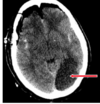

Which of the following mechanism of TBI is depicted in the CT?

1- Skull fracture

2- Contusion (bruise)

3- hematomas (blood clots)

4- lacerations (tear)

5- Diffuse axonal injury (nerve damage)

A